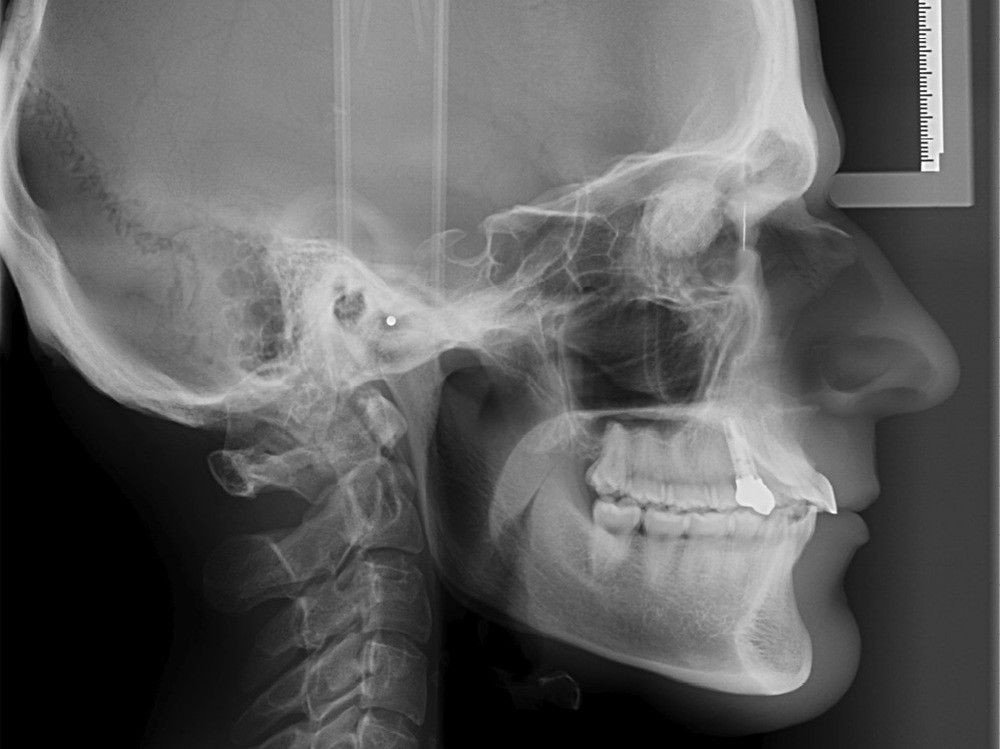

Après un an de traitement, une réévaluation est faite. De nouveaux clichés sont réalisés sur un nouvel appareil radiographique fraîchement installé (fig. 2). Les clichés obtenus sont de meilleure qualité et plus contrastés.

À l’examen de ces nouveaux clichés, une image radiologique de type « masse ronde » en regard des orbites se détache nettement. Immédiatement remontent mes souvenirs de cours de radio de l’examen du CECSMO. On nous apprenait à regarder la selle turcique et à reconnaître une tumeur. Une intime conviction s’impose : mon patient a une tumeur…

Je retourne immédiatement vers les premiers clichés avant traitement : l’image radiologique de la masse était déjà là !